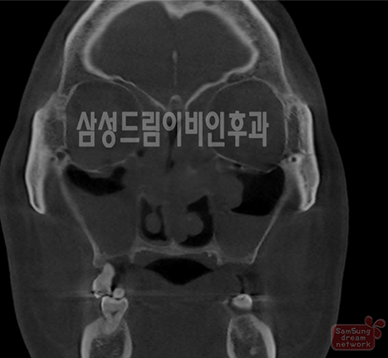

축농증 소견 코CT, 정상 소견 코CT